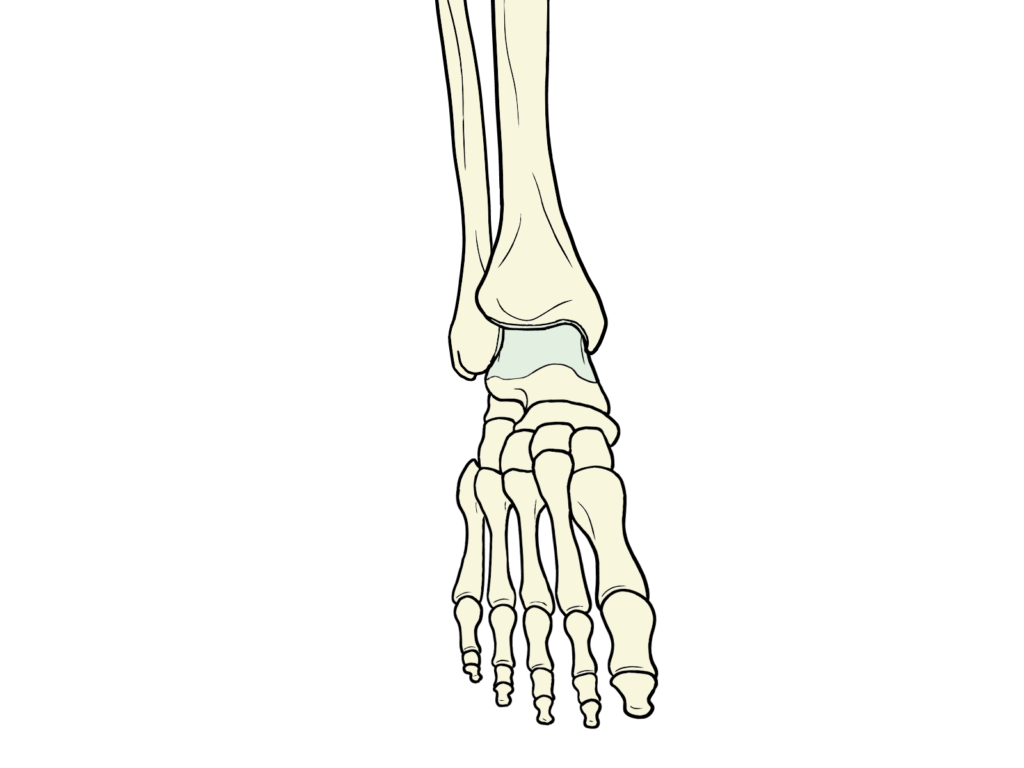

足首の安定を語る上で絶対に外せないのが、足首の関節の要となる「距骨(きょこつ)」です。

色が変わっているところが距骨です。